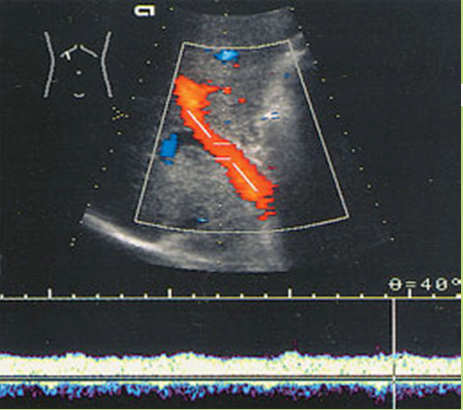

What is Portal venous hypertension?

This is an increase in portal venous pressure (above 10mmHg) or hepatic venous gradient (above 5mmHg).

What is the sonographic appearance of Portal venous hypertension?

Portal vein measures greater than 13mm

Collateral

circulation

Flow reversal

Ascites

Hepatosplenomegaly

What are the lab values that would suggest Portal venous hypertension?

↑Liver Enzymes

↓Platelet Count